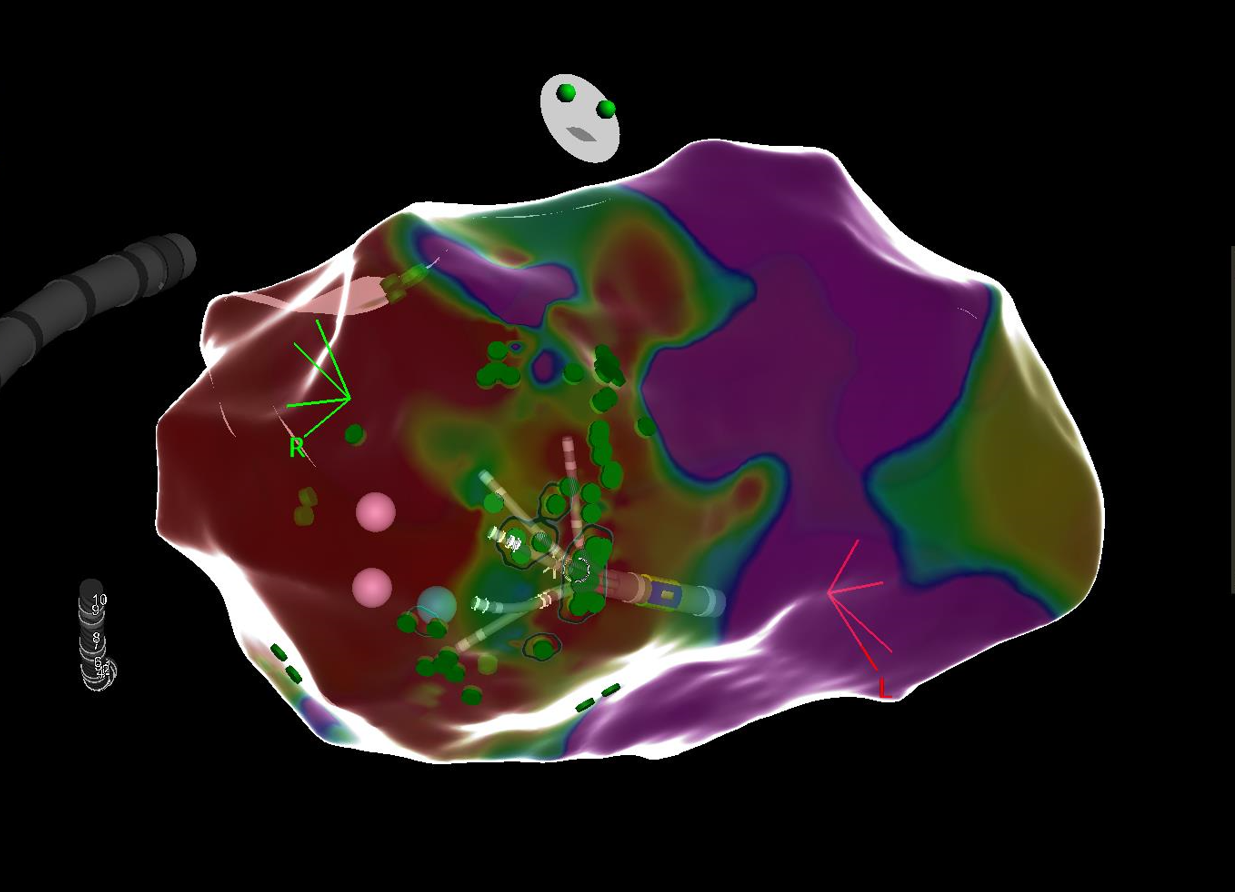

Vorhofflimmer Therapie - persönlich und individualisiert

Vorhofflimmern ist mit Abstand die häufigste Rhythmusstörung - jeder 3. Europäer wird im Laufe seines Lebens daran erkranken. Erfahren Sie mehr, wie wir Vorhofflimmern mit modernster Kathetertechnik behandeln - egal, ob Sie seit kurzem erkrankt sind, oder die Erkrankung bereits chronifiziert ist. Wir finden für Sie die richtige Technologie!

Links: Ultraschallbild eines Herzens, rechts: farbcodierte Substratkarte des Herzens